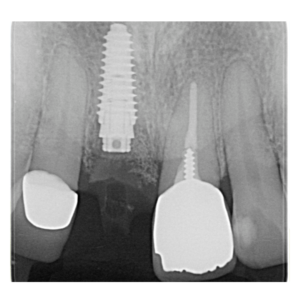

治療途中のインプラント症例

治療途中のインプラント症例です。

見た目を自然にしたい |

53歳 男性 |

1時間 |

¥350,000(税別) |

腫れ・痛み・神経損傷・インプラント周囲炎・骨吸収 など |